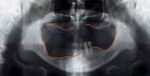

Fig. 7   Situation radiologique avant le traitement: les lignes rouges marquent les limites osseuses, les lignes bleue celles des tissus mous.

Le mode de résorption osseuse révélé par l’OPT (fig. 7) cor-                      restantes. En revanche, l’avantage de ces variantes de recons-

respondait aux caractéristiques décrites par Tolstunov (2007)                       truction réside dans le fait que le ligament parodontal et par

pour le syndrome combiné: présence de dents naturelles dans                         conséquent les capacités proprioceptives des deux dents se-

la partie antérieure du maxillaire inférieur, avec comme corol-                     raient conservées. A noter toutefois que tant les patients avec

laire une association possible avec une résorption osseuse dans                     des prothèses hybrides ancrées sur des implants que ceux avec

le segment des dents antérieures du maxillaire supérieur. Telle                     des prothèses hybrides ancrées sur des coiffes radiculaires pré-

était précisément la situation de ce patient: dans une localisa-                    sentent un seuil de sensibilité tactile active et passive nette-

tion directement supérieure aux dents 33 et 34 encore pré-                          ment supérieur à celui des patients complètement dentés (Van

sentes, présence de défauts osseux dans le maxillaire supérieur,                    Steenberghe & Jacobs 1991; Mericske-Stern 1994). Il semble que

de même que                                                                         l’activation de récepteurs muqueux et la présence d’une pro-

– du côté droit, résorption extrême de la crête osseuse posté-                      thèse totale dans le maxillaire antagoniste modifient la sensi-

rieure de la mandibule et                                                        bilité et la capacité discriminative. En conséquence, celles-ci

– du côté gauche, résorption osseuse dans les segments posté-                       sont également réduites sous des prothèses hybrides ancrées

rieurs et antérieur du maxillaire supérieur; dans le maxillaire                  sur des coiffes radiculaires (Mericske-Stern & Zarb 1996).

inférieur, absence de résorption la région dentée et résorp-                        Hug et coll. (2006) ont utilisé une échelle visuelle analo-

tion modérée de la crête postérieure (région 37, 38).                            gique (EVA) pour évaluer la satisfaction de patients avec trois